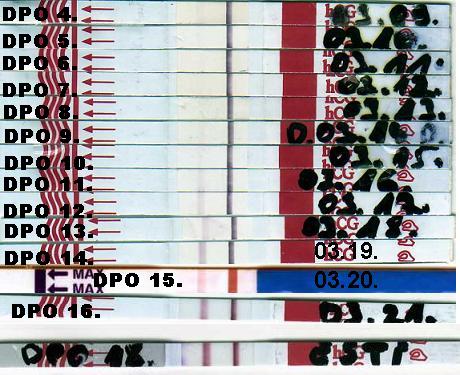

2008.03.20 11:25

2008.03.20 17:45

2008.03.21 08:41

2008.03.21 10:50

2008.03.21 14:30

2008.03.21 20:52

2008.03.21 23:37

2008.03.24 14:07

2008.03.24 16:29

2008.03.24 23:21

2008.03.25 11:45

2008.03.25 16:10

2008.03.25 16:23

2008.03.25 16:31

2008.03.28 11:36

2008.03.28 16:56